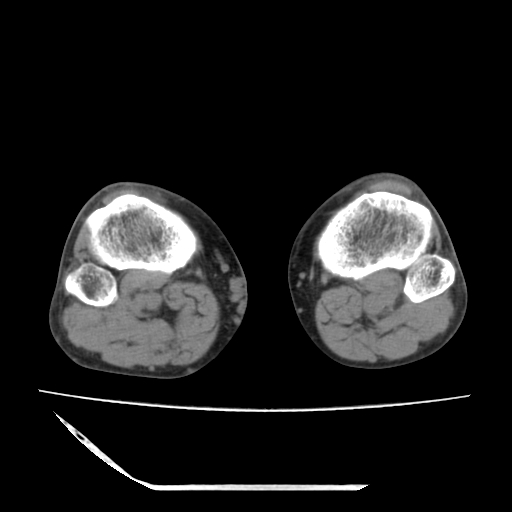

标题: CT13225:老年男性,左膝关节疼痛数月;请各位老师讨论。 [打印本页]

标题: CT13225:老年男性,左膝关节疼痛数月;请各位老师讨论。

骨质增生,骨性关节面硬化,关节积液,考虑退行性骨关节病

关节腔内少量积液,关节面退变。

双膝退变

骨质增生,骨性关节面硬化,关节间隙失常,关节积液,考虑退行性骨关节病.

骨质增生,骨性关节面硬化,关节积液,考虑退行性骨关节病。

这个病例诊断:退行性骨关节炎